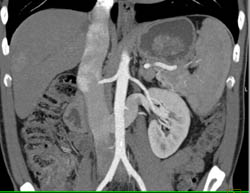

Focal Nodular Hyperplasia (FNH)